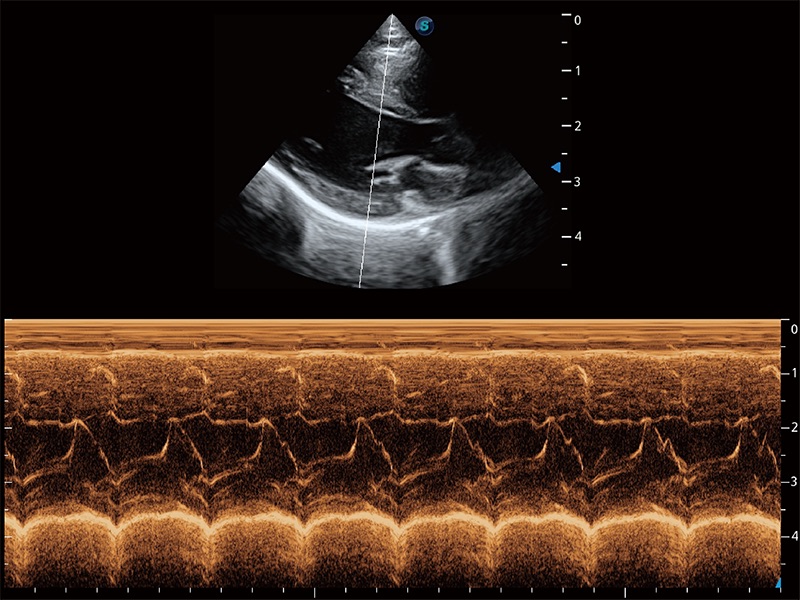

ProPet 80 配備了豐富的心臟探頭群、先進的成像技術(shù)和專業(yè)的心臟測量工具,可幫助動物醫(yī)生為不同體型和生理結(jié)構(gòu)的動物提供心臟和心肌功能的全面評估。

通過360度任意調(diào)節(jié)3條M型取樣線,在同一心動周期上觀察心臟不同位置的運動曲線,得到準確的心功能測量數(shù)據(jù),有效評估心肌運動及左心室功能。